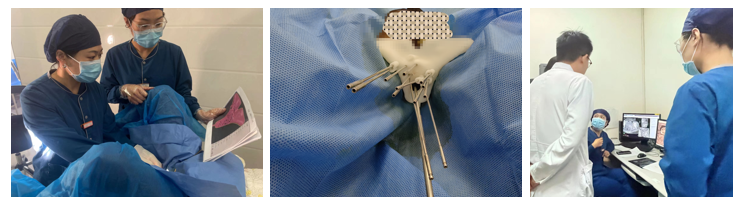

素股后装治疗室穆允凤副主任及其团队,综合评估患者病情及肿瘤情况后,首先将大小适合的普通阴道塞子置入患者阴道内进行首次CT图像采集,由后装医生在首次CT图像上进行靶区勾画,勾画出需要照射的肿瘤区域和需要保护的正常器官,接下来由物理师赵强重建出肿瘤与正常组织的三维模型,通过人工智能融合3D打印技术,将布源方案建成个体化的多通道内插植模具。3D打印模具制作完成后经过低温消毒处理,在核实各通道进针位置及深度后,接下来由后装医生操作,对该名患者实施了个体化3D打印模板引导下的插植操作。

(3D打印个体化定位模)

(定位模具引导、固定及计划沟通审核)